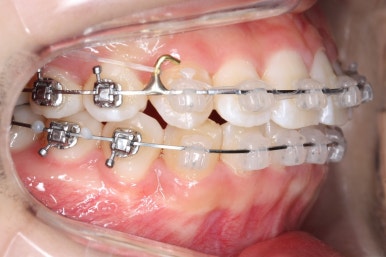

우선 윗니부터 가지런하게 합니다. 그리고 아랫니는 가지런하게 할 준비를 하죠.

화살표에 보이는 부착물의 이름이 바이트터보 입니다.

깊게 맞물리는 앞니, 즉 과개교합을 개선하기 위해 일시적으로 이용하는 장치입니다.

굉장히 효율적으로 과개교합을 개선할 수 있습니다.

아랫니에도 이제 장치를 붙였습니다.

과개교합인 채로 아랫니에도 장치를 붙이게 되면 아랫니 장치가 깨물려서 다 떨어지거나 부서지기 쉽습니다. 따라서 바이트터보는 굉장한 역할을 하게 됩니다.

눈으로 보기에는 과개교합이 개선이 된 것처럼 보이지만 아직은 아닙니다. 바이트터보가 남아있는 채로도 어금니가 맞물려야 진짜로 개선된 것이죠.